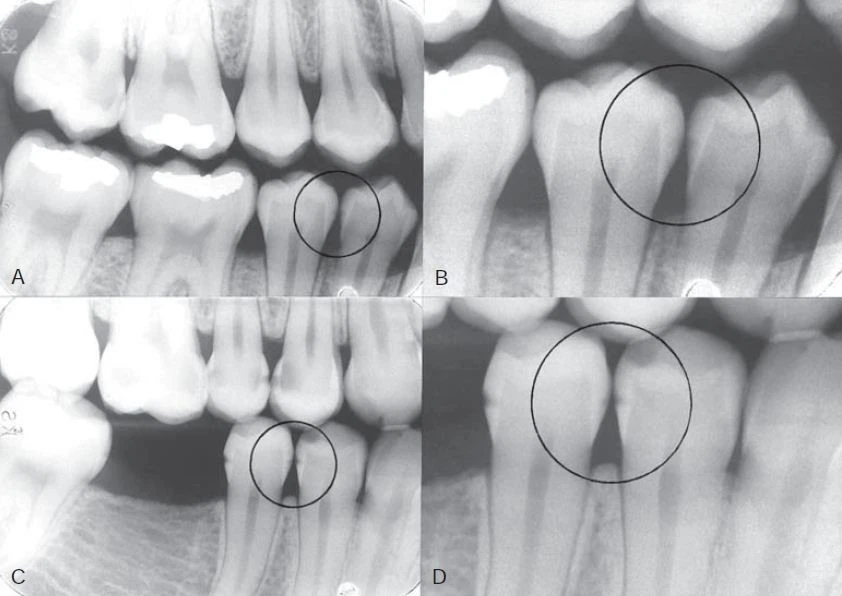

Hình 1. Quá trình mất khoáng ở mặt nhai và mặt bên đi từ men răng đến ngà răng và chạm vào tuỷ răng.

Hình ảnh thấu quang sớm của tổn thương trên men răng thông thường có hình tam giác với đáy rộng nằm trên bề mặt răng, mở rộng dọc theo trụ men, những hình ảnh phổ biến khác chẳng hạn như rãnh, một dấu chấm, một dải hoặc một đường mỏng. Khi quá trình mất khoáng hoá tiến triển đến đường nối men ngà, nó lan rộng dọc theo đường này, thường hình thành nên đáy của một tam giác thứ hai với đỉnh hướng về phía buồng tuỷ. Tam giác này thường có đáy rộng hơn ở men răng và tiến triển hướng về phía tuỷ răng dọc theo các ống ngà. Ngoài ra, cũng có thể thấy những hình dạng bất thường khác của quá trình mất khoáng.

Tổn thương liên quan đến tiếp xúc mặt bên hầu hết thường nằm ở vùng tiếp xúc. Thật sự rằng loại tổn thương này không bắt đầu bên dưới bờ nướu, giúp phân biệt với tổn thương sâu răng tại cổ răng. Cần chú ý kỹ đến bề mặt tiếp xúc bên nguyên vẹn gần với bề mặt răng có miếng trám vì thường bề mặt này có thể bị tổn thương khi trám răng và vì vậy có nguy cơ cao bị sâu răng.

Vì mặt tiếp xúc bên của vùng răng sau thường rộng, việc mất một lượng chất khoáng từ tổn thương sâu răng mới chớm và tiến triển của một tổn thương hoạt động thường khó phát hiện trên X quang. Tổn thương giới hạn trong phần men răng có thể không có dấu hiệu gì trên X quang cho đến khi 30% đến 40% quá trình mất khoáng xảy ra. Vì lý do này, độ sâu thật sự của tổn thương sâu răng thường sâu hơn so với hình ảnh thấy được trên X quang.

Thậm chí những nha sĩ nhiều kinh nghiệm cũng thường không đồng ý với việc có hay không có sâu răng khi kiểm tra trên một lần chụp X quang khi tổn thương chỉ giới hạn ở phần men răng. Đôi khi có thể phát hiện sai tổn thương sâu răng khi bề mặt răng không bị ảnh hưởng (kết quả dương tính giả). Nhiều hiện tượng hình thái chẳng hạn như những trũng và rãnh, chỗ lõm vùng cổ răng, hiệu ứng dải Mach, những bất thường về răng chẳng hạn như những rãnh giảm sản và những chỗ lõm do mòn răng cũng có thể giả dạng hình ảnh sâu răng. Trong những trường hợp mất khoáng không biểu hiện rõ trên X quang, việc không phát hiện được thương tổn được gọi là kết quả dương tính giả. Ngoài ra, những điểm tiếp xúc chồng lên nhau trên hình ảnh X quang có thể che lấp mất tổn thương. Khoảng một nửa tất cả những tổn thương mặt bên ở phần men răng không thể phát hiện được trên X quang.

Hình 11. A. Hình ảnh X quang của một răng đã được nhổ với tổn thương nằm ở ngà răng phía bên trái (vòng tròn). B. Răng được cắt và soi dưới kính hiển vi cho thấy tổn thương nằm ở cả hai bên, tổn thương bên phải chỉ nằm ở men răng (phần men răng phía bên trái răng bị vỡ trong quá trình cắt)